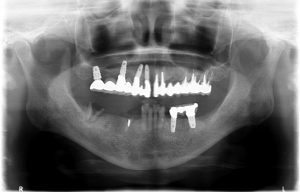

まずはレントゲン写真から

4年前に来院した時には右上、左下のブリッジが脱落し根は残せない状態でした。その後インプラント治療を選択、無事完了。

しかし定期検診にいらしていただけず。。2年。

次に来院された時は右下のブリッジが脱落し、またしても根は残せない状態になっていました。

再度右下3本と、左下1本インプラントを入れて無事治療は終了しました。